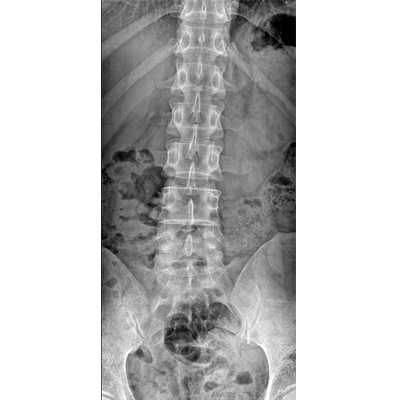

●探測器可以大范圍轉(zhuǎn)動,大尺寸有效探測面積,可滿足人體多部位攝影需求。